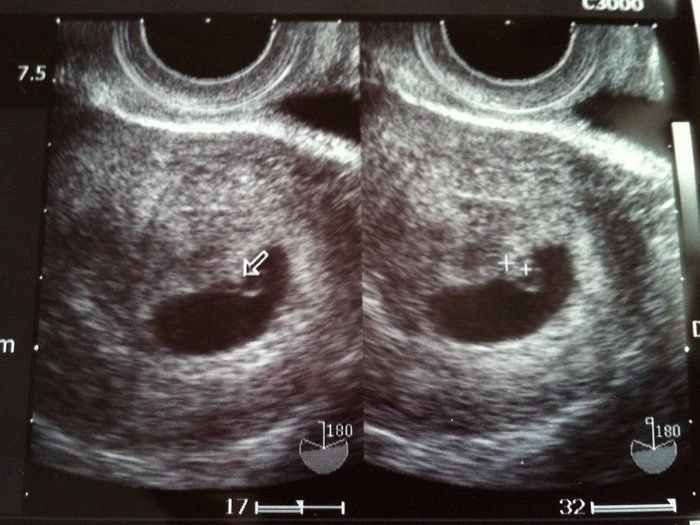

ママにエールさんの妊娠6週目のエコー写真

薄茶色のおりもの(出血)があり、気になって産院へ電話。「とりあえず、診察へ」と言われて受診しましたが、妊娠初期によくある程度の出血だから大丈夫とのこと。出血止めの薬だけ処方されました。ちょうどこの時、エコーで白い小さな粒を確認。「これが赤ちゃんに成長していきます」と先生に聞いて、愛しさでエコー写真をしばらく眺めていました。夫に見せたら、「ちっこい」と笑っていました。